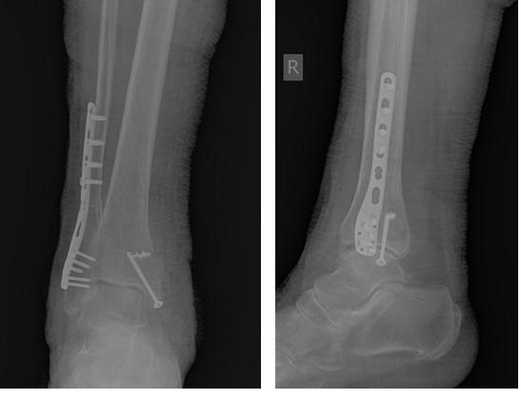

Пациент М. 1980 г.р., травму получил при падении на стопы с высоты 1,5 метра. Лечился по месту жительства (в травмпункте районной больницы) консервативно в гипсовой повязке в течение 14 дней. Консультирован в травматологическом отделении ФГБУ «УНИИТО им. В.Д. Чаклина» Минздрава РФ, предложено оперативное лечение. При поступлении кожные покровы стопы чистые, без признаков воспаления и сдавления тканей. Стопа отечна, уплощена. На рис. 1 представлены рентгенограммы пациента. Прооперирован через 2 недели после травмы. Операция состоит из двух этапов. Первый этап заключается в наложении дистракционного аппарата. Проводятся две спицы 1,8 мм во фронтальной плоскости: первая через нижнюю треть диафиза большеберцовой кости, вторая через бугор пяточной кости (рис. 2). Спицы фиксируются в дистракционном аппарате, выполненном из двух полуколец, соединенных между собой двумя телескопическими тягами. Особое расположение полуколец, фиксация спиц на концах полуколец, крепление кронштейнов для телескопических тяг обеспечивает тракцию пяточной кости в необходимом направлении с использованием минимального количества спиц и внешних опор при сохранении необходимого поля обзора для проведения рентгенологического и визуального контроля репозиции и фиксации. Второй этап - закрытая элевация импрессированной суставной поверхности и окончательная репозиция пяточной кости. Через разрез длиной до 1 см по латеральному краю ахиллова сухожилия (рис. 3) в месте его прикрепления к пяточной кости под соответствующий фрагмент подводится элеватор (рис. 4), манипуляцией которым устраняется смещение и выполняется провизорная фиксация спицами 1,5 мм (рис. 5). При сагиттальном раскалывании суставной фасетки целесообразно проведение одного-двух винтов субхондрально (рис. 6). Стержень вводится с дорзальной поверхности пяточной кости по ее оси через разрез до 2 см по предварительно сформированному остеотомом каналу (рис. 7, 8). Далее через проколы кожи с помощью кондуктора (рис. 9) выполняется запирание винтами с латеральной поверхности, внешнее устройство демонтируется. Достигнуто удовлетворительное стояние отломков (рис. 10).

Рис. 10. На рентгенограмме левой стопы в прямой и боковой проекциях определяется удовлетворительное стояние костных фрагментов на фоне металлофиксатора